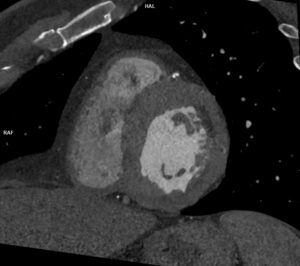

Discuţie caz nr 90: se evidențiază o soluție de continuitate la nivelul septului interventricular în treimea medie cu diametrul de 0.2 cm ce este restricționat de trabecule ventriculare drepte și de crista supraventricularis. La acest pacient a fost descoperire întâmplătoare, indicația de efectuare a examinării cardioCT era boală coronariana cronică.

DE LUAT ACASĂ!!! Un defect de sept interventricular mic, restricționat de trabeculele VSD, este un tip de VSD în care defectul este blocat parțial sau complet de fibrele musculare și crestele din ventriculul drept, limitând fluxul de sânge prin DSV și reducând potențial severitatea shuntului. Pentru evidențierea suntului este utilă completarea cu examinare cardio-RM pentru calcularea raportului Qp : Qs prin hărți de velocitate.